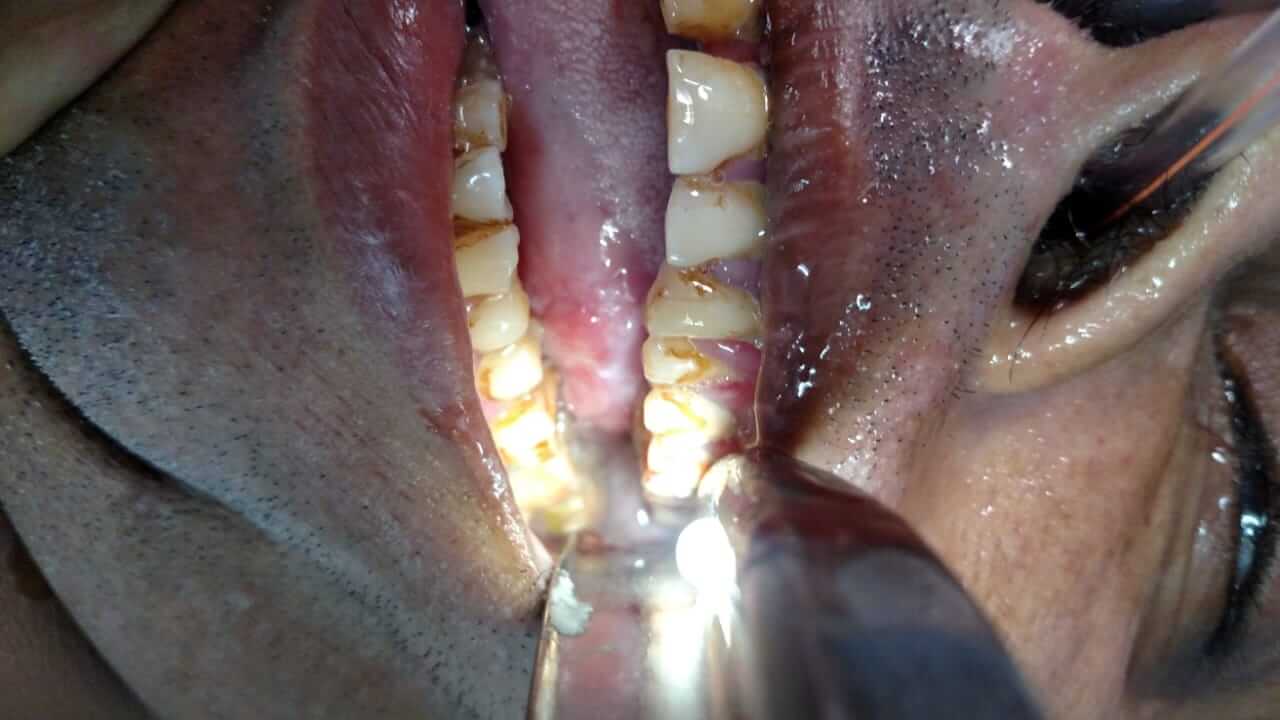

62 years old male suffering from left tongue lekoplakic lesion .wide excision done.leukoplakia is prone to develope cancer.histopathology shows verrucous lesion with severe fungal infection.